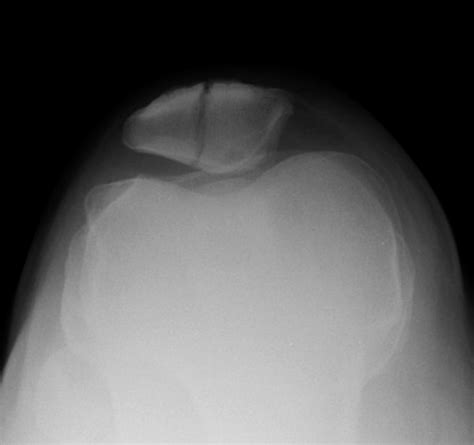

While only an X-ray or MRI can definitively diagnose a fracture, certain clinical signs are strongly associated with broken bones in the knee area. If you notice a combination of these, seek medical attention immediately.

When you arrive at the clinic or hospital, the medical team will likely perform a physical examination followed by diagnostic imaging. An X-ray is the gold standard for identifying fractures, but a CT scan may be required to assess the extent of the damage if the fracture extends into the joint space. Once the extent of the fractured knee symptoms is mapped, the doctor will determine whether non-surgical intervention—such as casting and bracing—or surgical fixation is required.